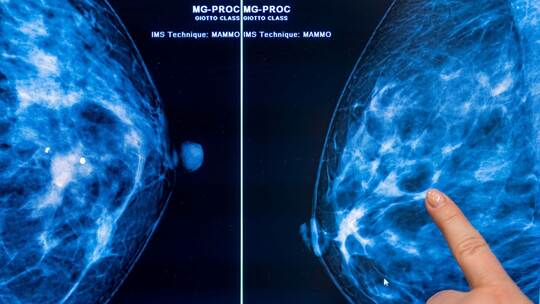

Das Mammografie-Screening für Frauen trägt einer Studie zufolge deutlich zur Senkung der Brustkrebs-Sterblichkeit in Deutschland bei. Das vor 20 Jahren eingeführte, von allen Krankenkassen angebotene Früherkennungs-Programm senkt die Todesfallzahlen und erhöht die Heilungschancen für erkrankte Frauen, wie das Bundesamt für Strahlenschutz (BfS) mitteilte. Unter den Teilnehmerinnen war die Brustkrebs-Sterblichkeit demnach über einer Nachbeobachtungszeit von bis zu 10 Jahren um 20 bis 30 Prozent geringer als bei den Nichtteilnehmerinnen.

Mit einer Mammografie lassen sich Tumore oft finden, bevor sie sich ertasten lassen – und je früher ein Karzinom erkannt wird, desto besser sind die Heilungschancen. Fortgeschrittener Brustkrebs, bei dem es bereits Metastasen gibt, sei nach wie vor in der Regel nicht heilbar, erklärte Klaus Kraywinkel, Leiter des Zentrums für Krebsregisterdaten am Robert Koch-Institut (RKI).

Im Zuge des Programms können Frauen im Alter von 50 bis 75 Jahren alle zwei Jahre eine Röntgen-Untersuchung der Brust zur Früherkennung in Anspruch nehmen. Bundesweit gibt es laut BfS 95 zertifizierte Screening-Zentren. Frauen, bei denen Symptome bestehen oder ein Verdacht auf Brustkrebs vorliegt, erhalten Mammografien zudem im Rahmen der allgemeinen Versorgung. Der Effekt dieser Untersuchungen wurde in der Studie nicht untersucht.